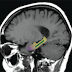

Brain imaging and memory tests were administered to each participant before and after the study. The brain imaging measured blood volume in the dentate gyrus, a measure of metabolism, and the memory test involved a 20-minute pattern-recognition exercise designed to evaluate a type of memory controlled by the dentate gyrus.

"When we imaged our research subjects' brains, we found noticeable improvements in the function of the dentate gyrus in those who consumed the high-cocoa-flavanol drink," said lead author Adam M. Brickman, PhD, associate professor of neuropsychology at the Taub Institute.

Two innovations by the investigators made the study possible. One was a new information-processing tool that allows the imaging data to be presented in a single, three-dimensional snapshot, rather than in numerous individual slices. The tool was developed in Dr. Small's lab by Usman A. Khan, an MD-PhD student in the lab, and Frank A. Provenzano, a biomedical engineering graduate student at Columbia. The other innovation was a modification to a classic neuropsychological test, allowing the researchers to evaluate memory function specifically localized to the dentate gyrus. .